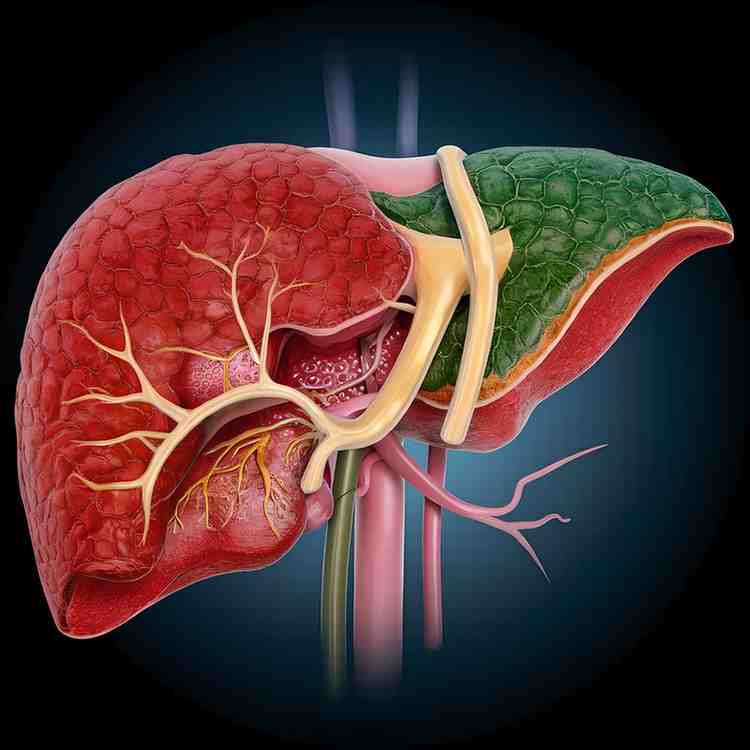

लिवर हमारे शरीर का एक बहुत महत्वपूर्ण अंग है, जो पाचन में मदद करना, खून को साफ़ करना, दवाओं और टॉक्सिन को बाहर निकालना तथा ऊर्जा को स्टोर करने जैसे कई काम करता है। जब किसी वजह से लिवर की कोशिकाएँ सूजने लगती हैं और उसमें इंफ्लेमेशन पैदा हो जाता है, तो इसे लिवर सूजन भी कहा जाता है। अगर लिवर में सूजन होने पर उसकी काम करने की क्षमता समय के साथ कम होने लगती है तो इसका असर पूरे शरीर पर पड़ने लगता है, शरीर में थकान और इम्यून सिस्टम प्रभावित होता है और विषैले तत्व शरीर में जमा होने लगते हैं।

बहुत बार ये सवाल कई लोगों को भ्रम में डाल देता है कि लिवर सूजन और फैटी लिवर एक जैसी समस्या नहीं हैं, लेकिन दोनों आपस में जुड़ी हुई समस्याएँ हैं और अक्सर यह सवाल बहुत लोगों को भ्रम में डालता है। लिवर सूजन और फैटी लिवर एक जैसी नहीं हैं, लेकिन दोनों आपस में जुड़ी हुई समस्याएँ हैं। फैटी लिवर में लिवर की कोशिकाओं में जरूरत से ज्यादा चर्बी जमा होने लगती है और जब यह चर्बी लिवर में सूजन पैदा करने लगती है, तब यह स्थिति लिवर सूजन या फैटी लिवर हेपेटाइटिस में बदल जाती है। यानि हर फैटी लिवर में सूजन हो यह ज़रूरी नहीं है, लेकिन जब फैटी लिवर को समय रहते कंट्रोल नहीं किया जाता, तो वह लिवर सूजन का रूप ले सकता है।